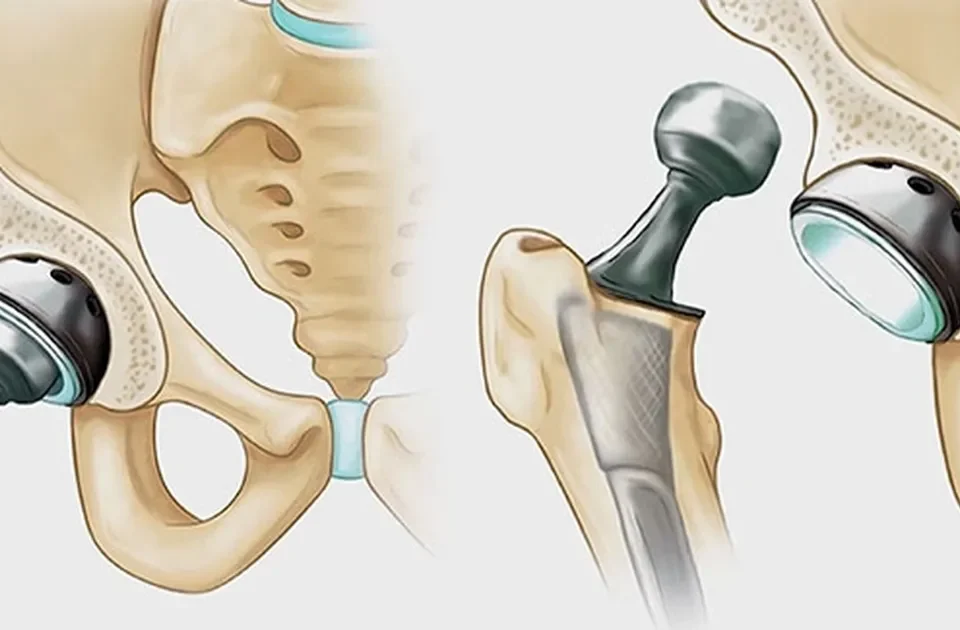

بعد از جراحی تعویض مفصل ران چه باید کرد؟

عمل شکستگی استخوان ران با روش «میله داخل استخوان ران» یکی از روش های مؤثر و رایج در درمان این نوع شکستگی ها است. در این روش، میله ای فلزی در داخل کانال مرکزی استخوان ران قرار داده می شود تا قطعات شکسته را در جای خود ثابت نگه دارد. این عمل موجب پایداری بهتر استخوان، کاهش درد پس از جراحی، و تسریع روند جوش خوردن و بازگشت بیمار به فعالیت های عادی می شود. استفاده از این تکنیک به دلیل نتایج موفق و عوارض کم، یکی از انتخاب های اصلی در درمان شکستگی های شدید استخوان ران به شمار میآید.